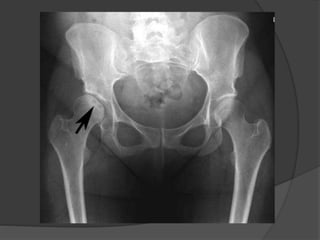

AP radiographic view of the pelvis shows flattening of the outer portion of

the right femoral head from avascular necrosis, with adjacent joint space

narrowing, juxta-articular sclerosis, and osteophytes representing

degenerative joint disease (stage IV)

AP radiographic viewof the pelvis shows flattening of the outer portion of the right femoral head from avascular necrosis, with adjacent joint space narrowing, juxta-articular sclerosis, and osteophytes representing degenerative joint disease (stage IV)